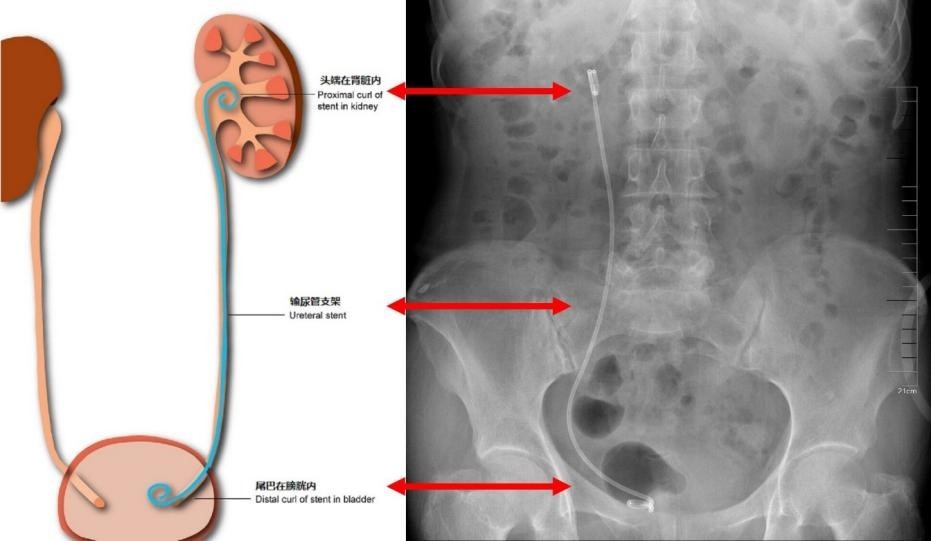

肾结石手术医生通常会在术后为患者放置一根“输尿管支架”——这就是我们说的“细管子”。它是一种细长柔软的管状材料,临床也叫“猪尾巴管”。两端卷曲,一端位于肾盂,一端位于膀胱,从而在肾脏与膀胱之间建立起一个稳定的“排水通道”。它能有效保证尿液顺利流动,缓解术后水肿或炎症带来的梗阻。